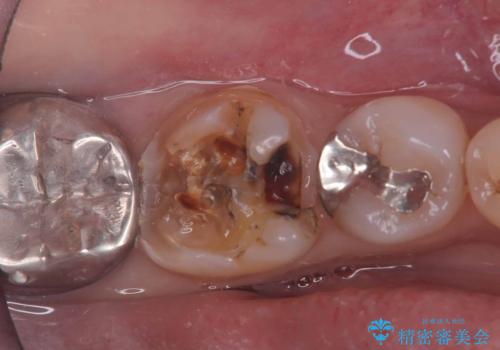

- 銀歯の下の虫歯です。お写真で分かるように広範囲で深い虫歯でした。

1歯はオールセラミッククラウンもう1歯はセラミックインレーで治療を行いました。